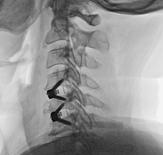

With degeneration of the joints between the vertebra, there is some collapse of the intervertebral disc and the resulting coming together of the vertebrae , along with thickening of the ligaments and overgrowth of the bone create a situation whereby the space available within the canal and foramen is reduced, thereby compromising the nervous structures.

This condition causes a situation of chronic nerve dysfunction called spinal canal stenosis.

Since the vertebral joints are most mobile at the cervical and lumbar levels, most of the degenerative changes occur at these level and hence , the condition of spinal canal stenosis mostly involves the neck and the low back.